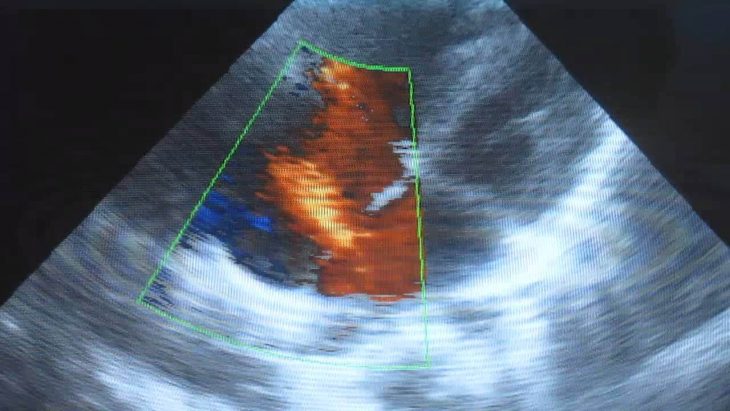

Открытое овальное окно в сердце: причины, симптомы, лечение и прогнозы Автор Полина Корректор | дата обновления 03.03.2015Мой мирВконтактеОдноклассникиОткрытое овальное окно в сердце: причины, симптомы, лечение и прогнозы Рубрика: Поделись в соцсетяхВконтактеОдноклассники